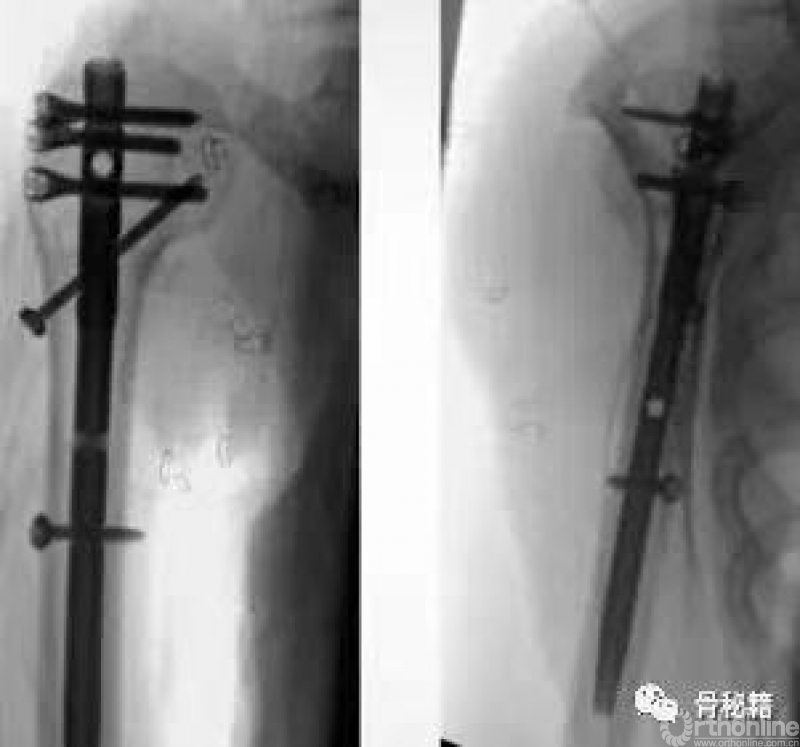

这是一个我们常见的肱骨近端骨折,我们可以看到外侧的大结节粉碎

中间有很多头内的缺损,常见的固定是将外侧复位之后通过钢板在外侧对剩余的头进行固定,这种偏心的固定在骨缺损的情况下通常很容易失败。

而我们应用髓内钉就是另外一种情况,通过头上较好骨质对主钉的把持来维持整个固定,这个病例为了很好的控制头的固定,使得进针点非常靠内,这样才能把持主头的骨折块,通过主钉来重建生物力学的稳定性,再通过锁定来重建大结节的部位,相对来说失败的几率更小一些

在复位好的基础上,植入合适的主钉导针

导针一旦植入,这个手术就完成了一半了

剩下就按照步骤进行